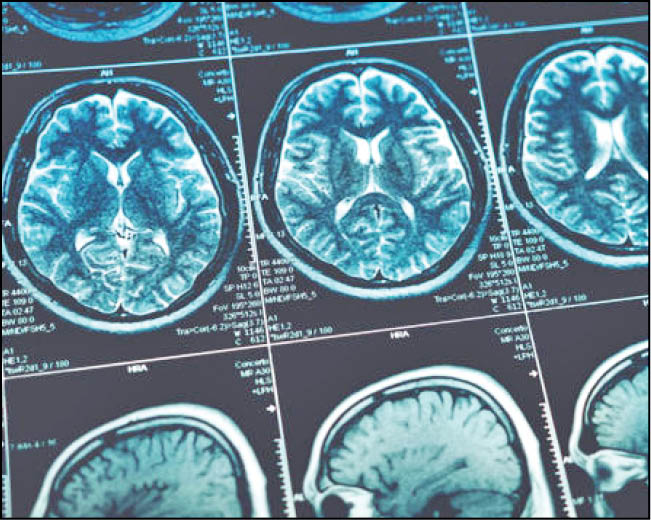

مطالعه‌ای در بریتانیا نشان داده که یک نفر از هر 7نفری که مورد بررسی قرار گرفته اند، ۱۲ هفته پس از مثبت‌شدن تست کووید، علائمی ازجمله مشکلات شناختی داشته اند. تحقیقی که اخیرا با تصویربرداری مغز همراه بوده است، نشان داد که حتی کووید خفیف  می‌تواند باعث کوچک‌شدن مغز شود. از 401فرد شرکت‌کننده در این مطالعه، فقط 15نفر در بیمارستان بستری شده بودند.

برای مشخص کردن نوع و میزان این نقایص شناختی و درک بهتر رابطه آنها با شدت بیماری در مرحله حاد و مشکلات سلامت روانی، داده‌های 46بیمار سابق کووید تجزیه و تحلیل شد. همه آنها در بیمارستان بستری شده بودند. شرکت‌کنندگان به‌طور متوسط 6ماه پس از بیماری حاد خود با استفاده از پلتفرم Cognitron تحت آزمایش‌های شناختی کامپیوتری دقیق قرار گرفتند. همچنین سطوح اضطراب، افسردگی و PTSD آنها اندازه‌گیری شد. بازماندگان کووید دقت کمتری داشتند و نسبت به گروه کنترل همسان واکنش کندتری داشتند. در نتیجه این مقایسه مشخص شد که میزان از دست دادن شناخت به‌طور متوسط مشابه با 20سال پیری، بین 50تا 70سال است. این معادل از دست دادن 10امتیاز IQ است. درحالی‌که افرادی که از کووید شدید بهبود یافته‌اند می‌توانند طیف وسیعی از علائم سلامت روانی ضعیف مانند افسردگی، اضطراب، استرس پس از سانحه، انگیزه پایین، خستگی، خلق‌وخوی ضعیف و خواب آشفته را داشته باشند اما نمی‌توان این علائم را به اختلال و نقص شناختی مرتبط دانست.